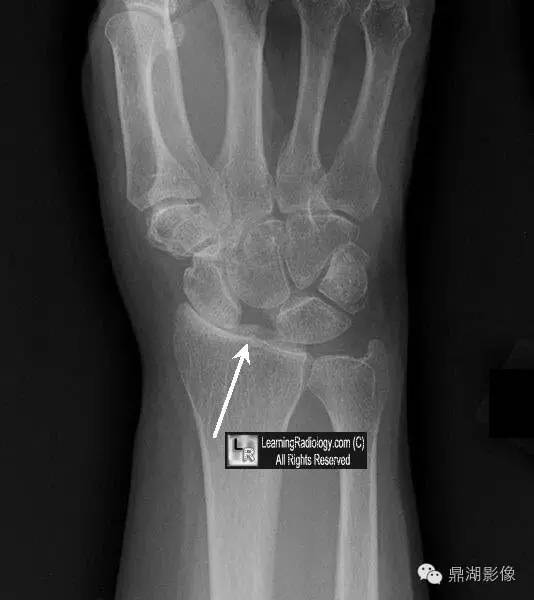

影像表现:当舟月骨分离、舟月骨间韧带撕裂所致腕关节正位片或CT冠状位示舟月骨间隙增宽,形似稀疏的牙缝。

(1)舟月骨间间隙>2mm为可疑分离,如>4mm即可诊断。

(2)皮质环征,环下界与舟骨近极关节面的间距<7mm。